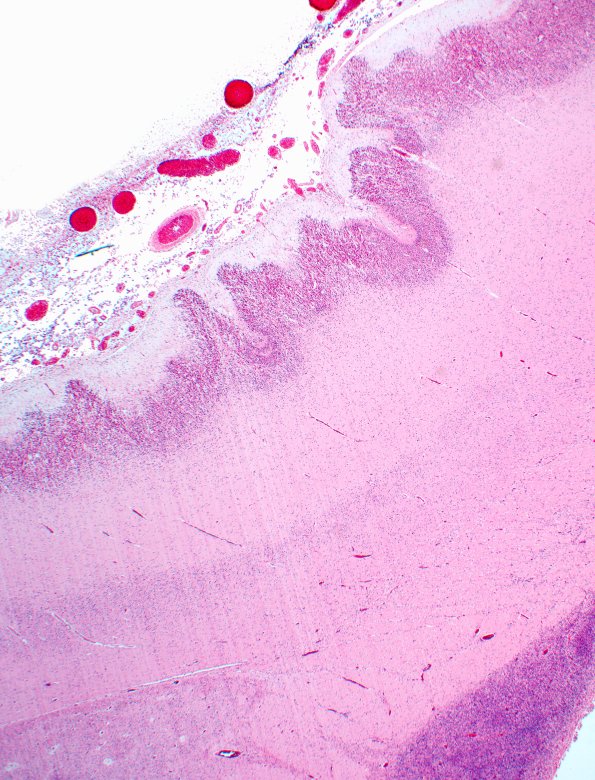

Polymicrogyria

12A2 PMG New (Case 12) H&E 2X A

Prior CMV encephalitis, culture proven, resulted in marked polymicrogyria. (H&E)